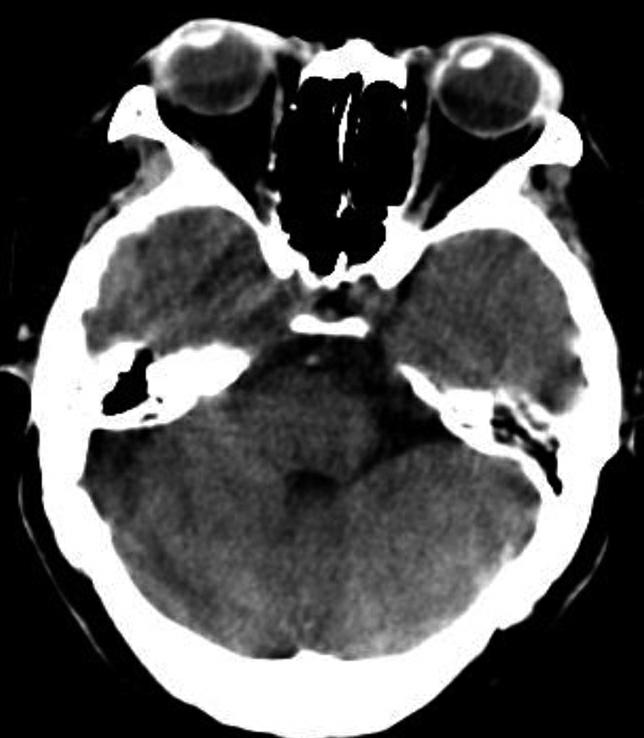

破裂孔、卵圆孔、棘孔及斜坡等均为重要的解剖结构,临床常见疾病如鼻咽癌常侵犯上述结构(图1-2-3)。颈静脉孔区较常见的肿瘤为颈静脉球瘤,常伴有颈静脉孔及其邻近骨质的破坏(图1-2-4)。

图1-2-4 右侧颈静脉球瘤

A.横断面(骨窗);B.横断面

右侧颈静脉孔区不规则骨质破坏(箭),局部见软组织肿块(☆)